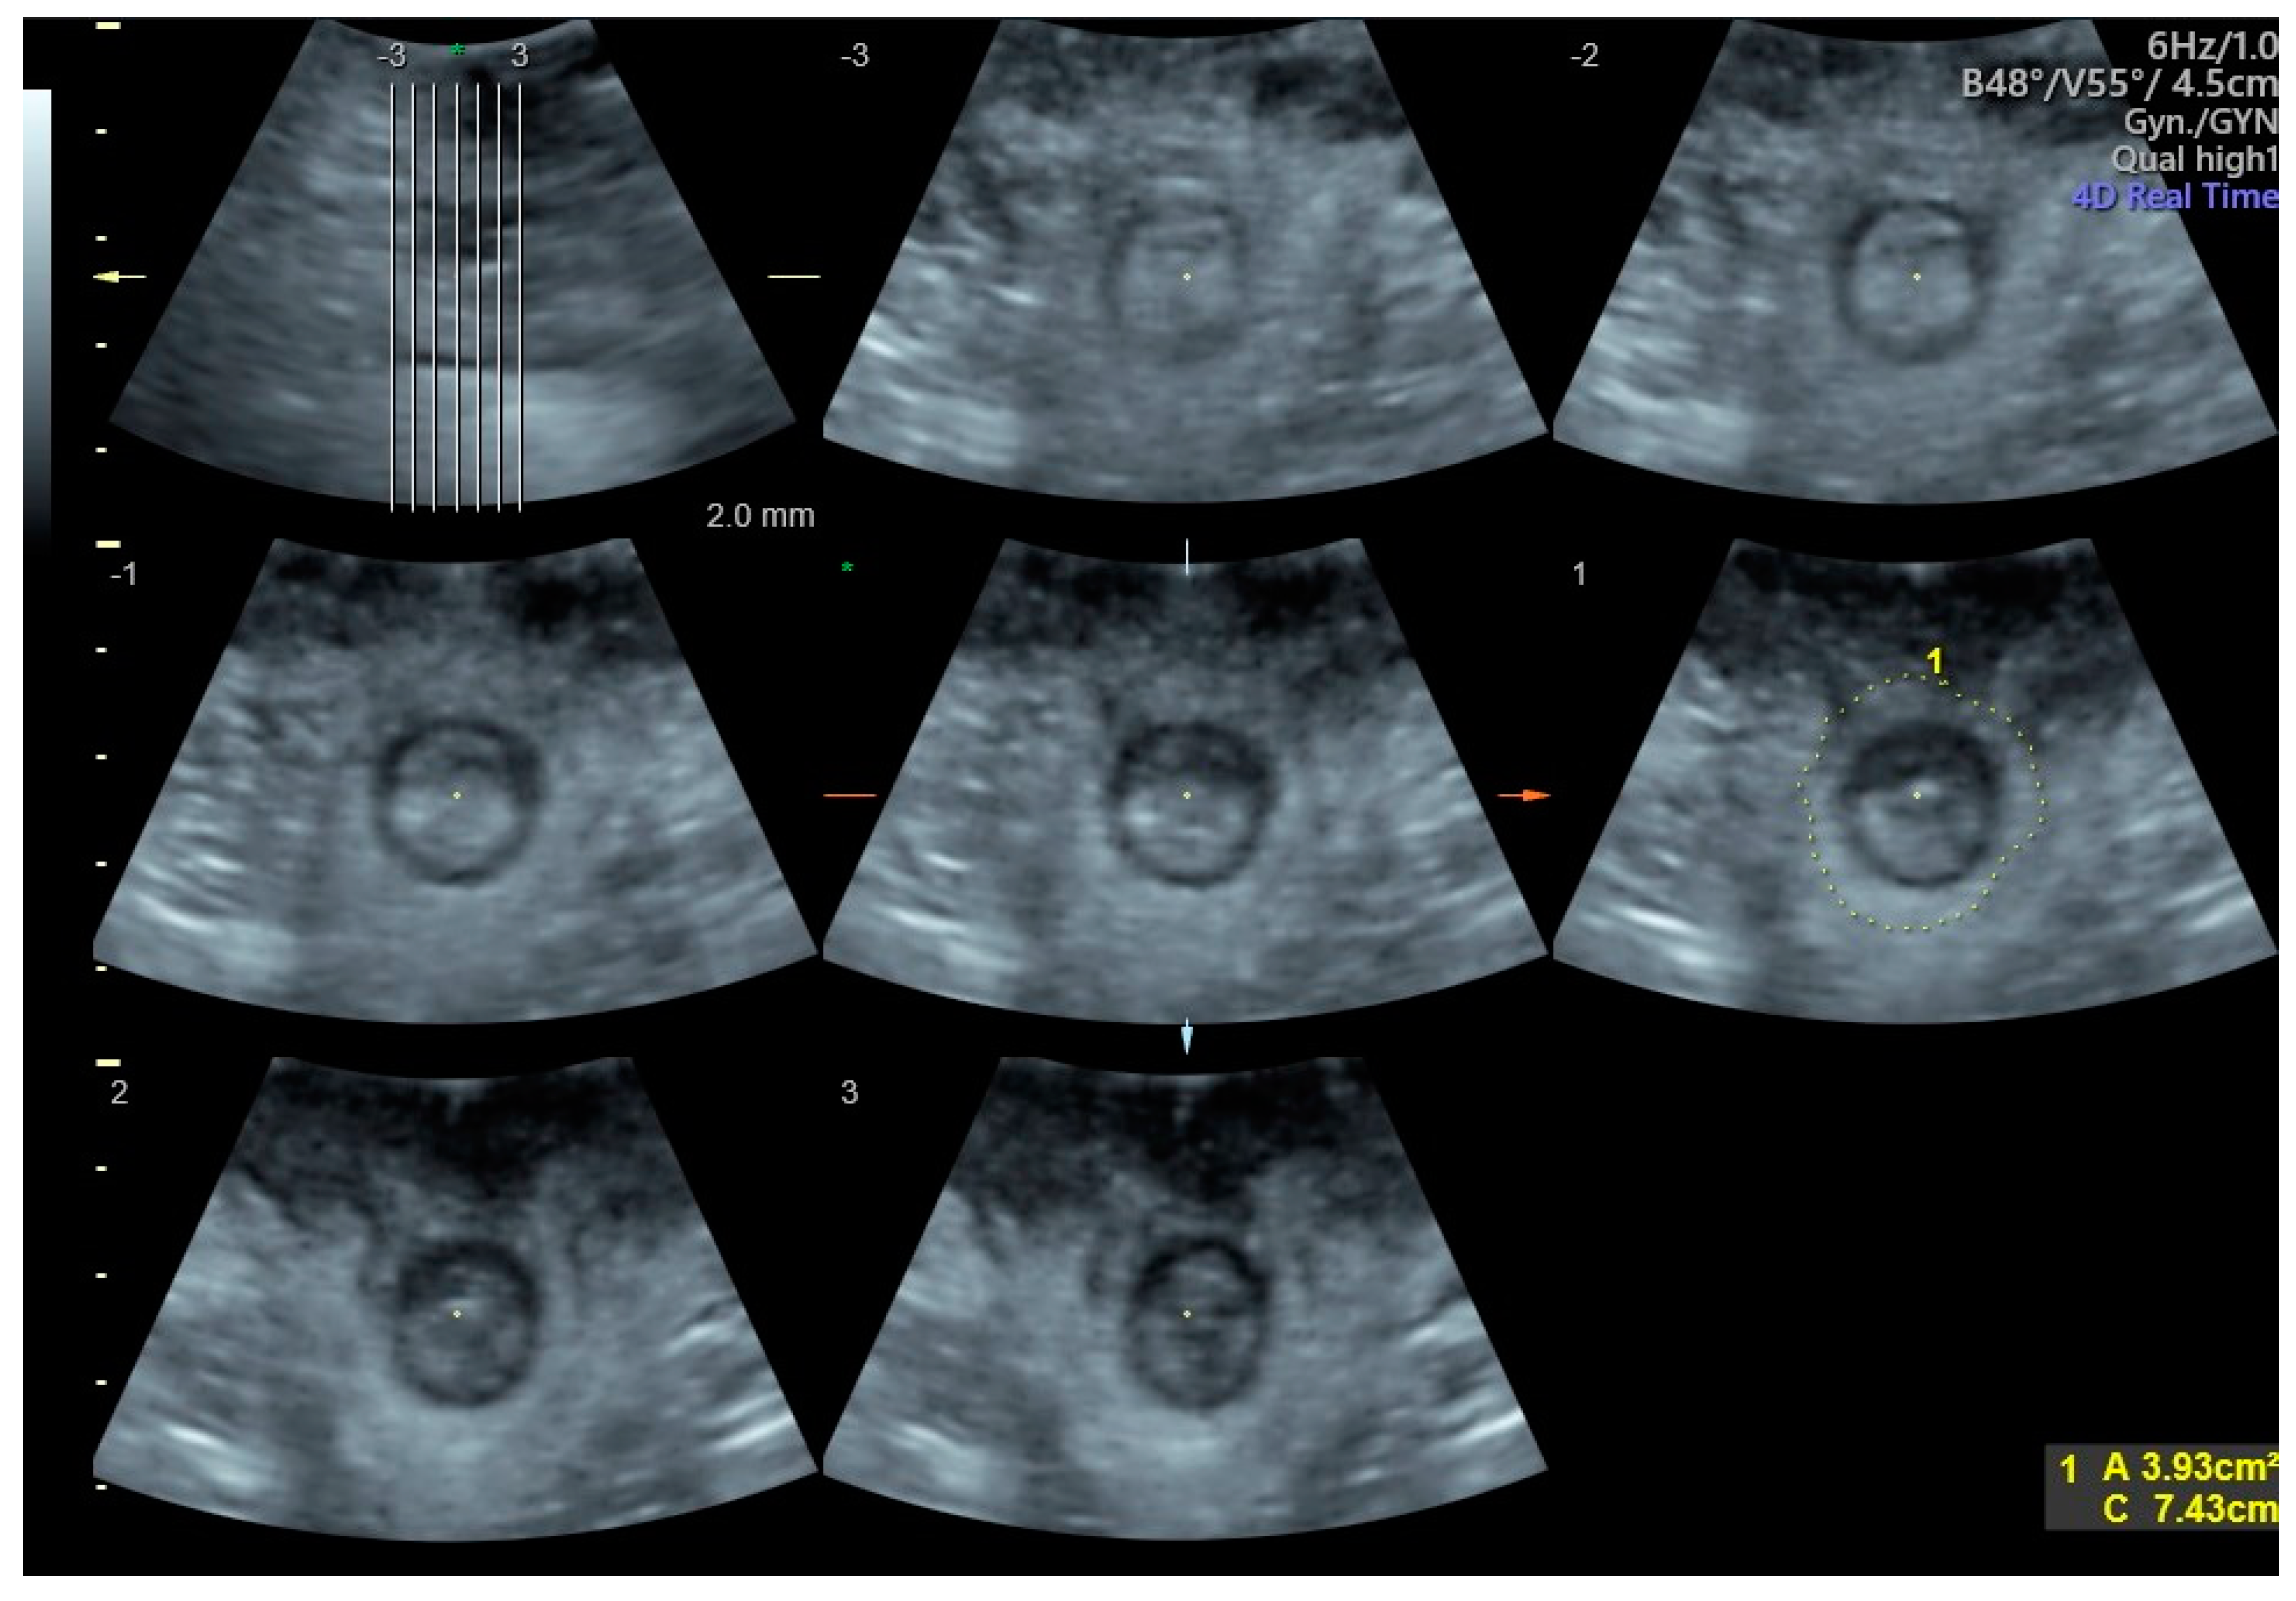

2. Materials and Methods

Figure 1. Visualization of the anal sphincter and measurement of its area using tomographic ultrasound imaging (TUI). The slices range from −3 to +3, and the green spot (*) marks the 0 point.